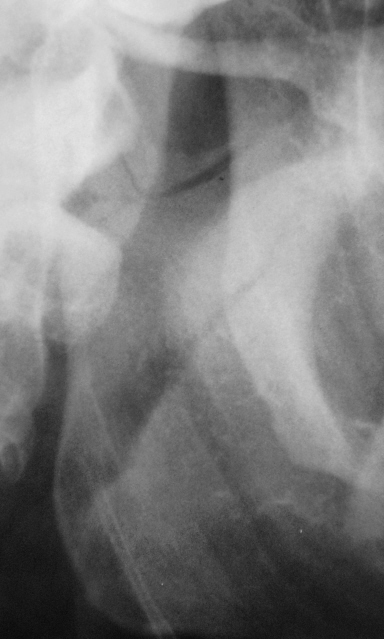

Ваше мнение коллеги.

на мой взгляд здесь перелом суставного отростка